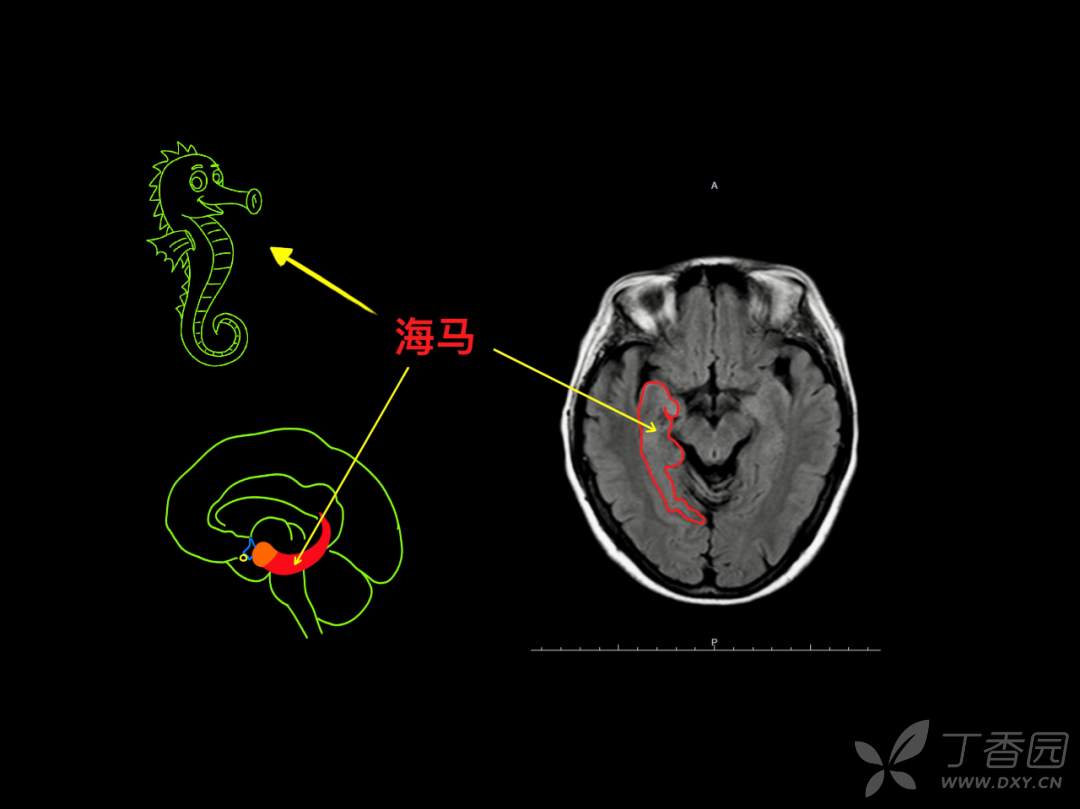

神经专业,要求「定位和定性」,先定位,后定性。与 CT 相比,颅脑 MR 可以更多、更清晰的呈现脑组织的解剖结构,神经专业的医生如何在颅脑 MR 的断层成像上去定位?

要么,你有「超级大脑」可以一层层的去记忆,「太难了」!那你也许会喜欢基于 「keypoint」的阅片方法,比如「苹果」外形、「Ω 征」、「M 征」等。本篇精华版 essay 希望给大家带来不一样的 MR 阅片技巧。

神经内科存在很多“征”,有助于帮助大家记忆!